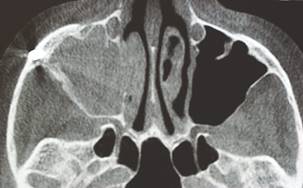

The presence of sinus pathology should be detected early, since the medical history, to avoid late complications associated with the implants. Chronical sinusitis, allergic episodes or other sinus pathologies deserve preview multidisciplinary approach with otorhinolaryngologist. Sinus approach, through of a bone window with rupture or removal sinusal membrane is controversial. The access and removal of sinusal membrane, allowing view and irrigation during the insertion of the implant are justified. Besides, they offer access to sinusal pathologies like polyps or cysts eventually find inside the maxillary sinus (Fig. 4).